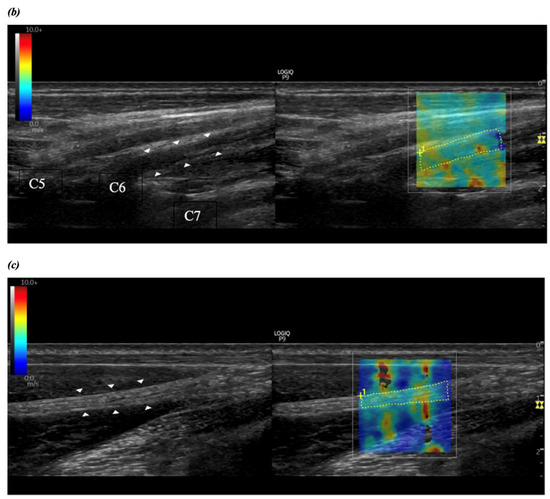

2.2.2. Brachial Plexus Imaging

2.2.3. Shear Wave Elastography and Ultrasound Measurements